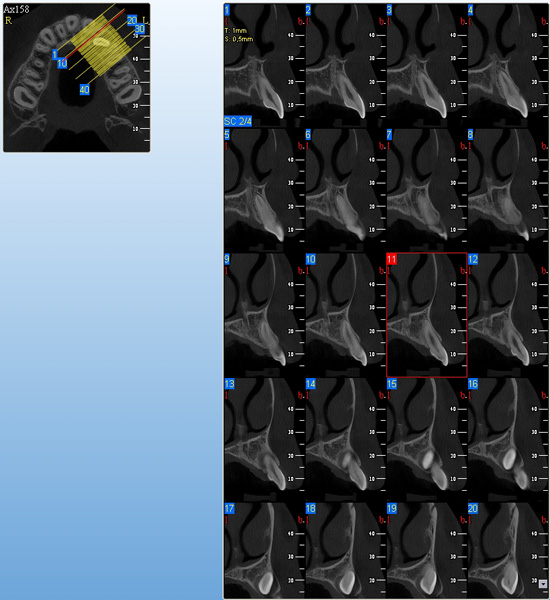

3D DVT - NewTom

Je speciální zubní digitální tříprostorový tomograf (3D), který umožňuje na základě jediného

snímkování vytvořit všechny typy RTG zobrazení, které jsou pro lékaře potřebné. Díky používané technologii tzv. „kuželového paprsku“ a speciálním senzorům je

výrazně zmenšená dávka záření - o více jak 80% proti klasickému CT vyšetření. To je významné zejména u dětí. Pomocí tohoto přístroje je možné zjisti skutečnou situaci v čelistních kostech pacienta tedy množství kosti - můžeme změřit skutečnou šířku i výšku kosti, i kvalitu kosti (hustotu) v místě uvažované implantace. 3D (tříprostorové) zobrazení umožňuje zvýšit prostorovou představu operatéra ještě před vlastní operací a zároveň pacientovi lépe objasnit a ukázat oblast plánovaného zavedení implantátu.

Pacient „neumí číst“ RTG snímky, ale díky 3D zobrazení vidí „svoji skutečnou čelist“

- např. jak je nízká či úzká, vidí průběh nervu nebo velikost čelistní dutiny, což mu umožní i pochopení nutnosti v některých případech provést pomocné zákroky ještě před vlastním zavedením implantátu (viz. kostní štěp, sinus lift, kostní granulát...).

Vyšetření pomocí tohoto přístroje používáme i ve stomatochirurgii (zlomeniny čelistí, zuby moudrosti, cysty, onemocnění čelistního kloubu), ortodoncii (retinované zuby, nadpočetné zuby), parodontologii atd.